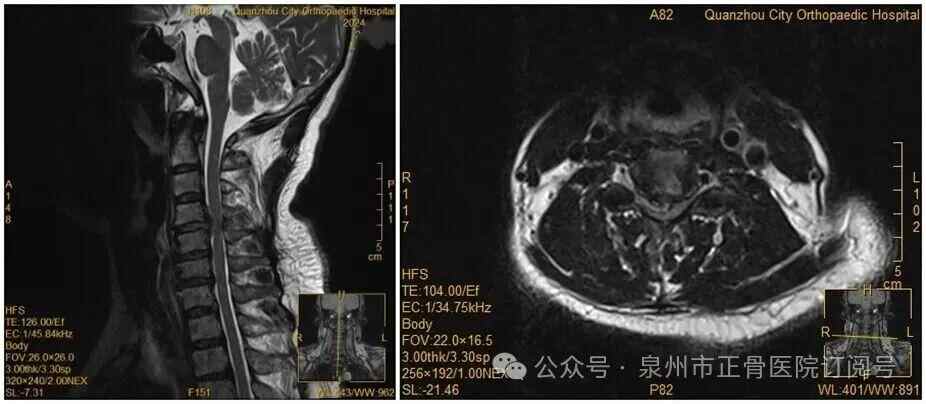

王女士术前MRI

没想到,会诊当晚,王女士翻身拿手机的瞬间,双手突然失去知觉——关键肌肌力降至1级或0级,确诊为瘫痪。“推测是翻身时,脱出的椎间盘突然进一步卡压到脊髓神经,引发了急性症状。”医生表示。